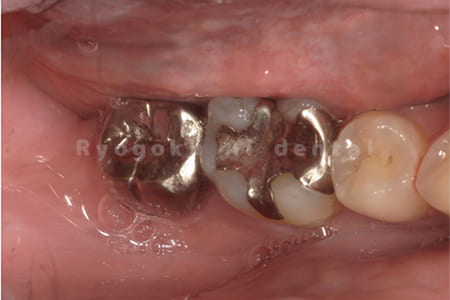

Case10

- 右下6番 重度カリエス

- 右下8を右下6へ移植に自家歯牙移植

- 治療期間

-

- 220,000円

右下の銀歯が外れかかっているとのことでご来院された患者様です。虫歯が大きく、かつ歯が割れており、保存不可能と判断し、親知らずの移植を行いました。

<リスク・副作用>

治療後、痛みや違和感、出血、腫れなどが出る事があります。喫煙者、糖尿病などの方の場合、歯が生着しない場合があります。